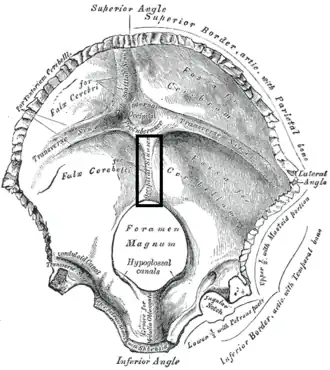

Occipital bone. Inner surface. (Position of internal occipital crest labeled as occipital sinus at center.) | |

Base of the skull. Upper surface. (Internal occipital crest visible below foramen magnum.)

Base of the skull. Upper surface. (Internal occipital crest visible below foramen magnum.) -